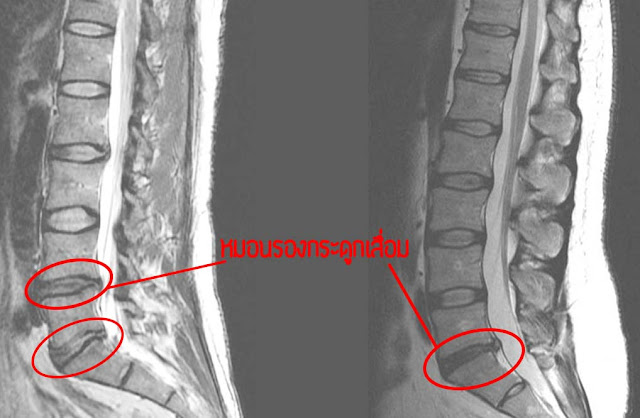

ภาพ MRI หมอนรองกระดูกทรุดตัว